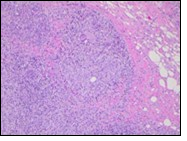

Figure 1.Granulomatous mastitis with the configuration of epitheloid cell granuloma and a lymphoid and plasma cell infiltrate9.

Granulomatous  mastitis with the configuration of epitheloid cell granuloma and a lymphoid and plasma cell infiltrate9.

Core needle biopsy of idiopathic granulomatous mastitis enunciates multiple aggregates of non- caseating epitheloid cell granulomas within and encompassing breast lobules, constituted of epitheloid histiocytes, lymphocytes, neutrophils and multinucleated giant cells. Granulomatous inflammation is predominantly lobulo-centric. The inflammation is preponderantly composed of lymphocytes, plasma cells, epitheloid histiocytes, multinucleated giant cells and neutrophils. Neutrophils can configure micro-abscesses and encompass vacant micro-cystic cavities, morphological features which are in common with cystic neutrophilic granulomatous mastitis. Non specific lobulitis along with a lymphoid and plasma cell infiltrate accompanies the granulomatous inflammation. Necrosis is usually absent. Neutrophilic micro-abscesses can be accompanied by fistula formation 4, 5.

Multinucleated giant cells are detected in an estimated three fourths (78.5%) instances. Plasma cells are discernible in around half (53.9%) of the subjects and usually appear at the margins of cystic vacuoles with centric accumulation of neutrophils within the granulomas.